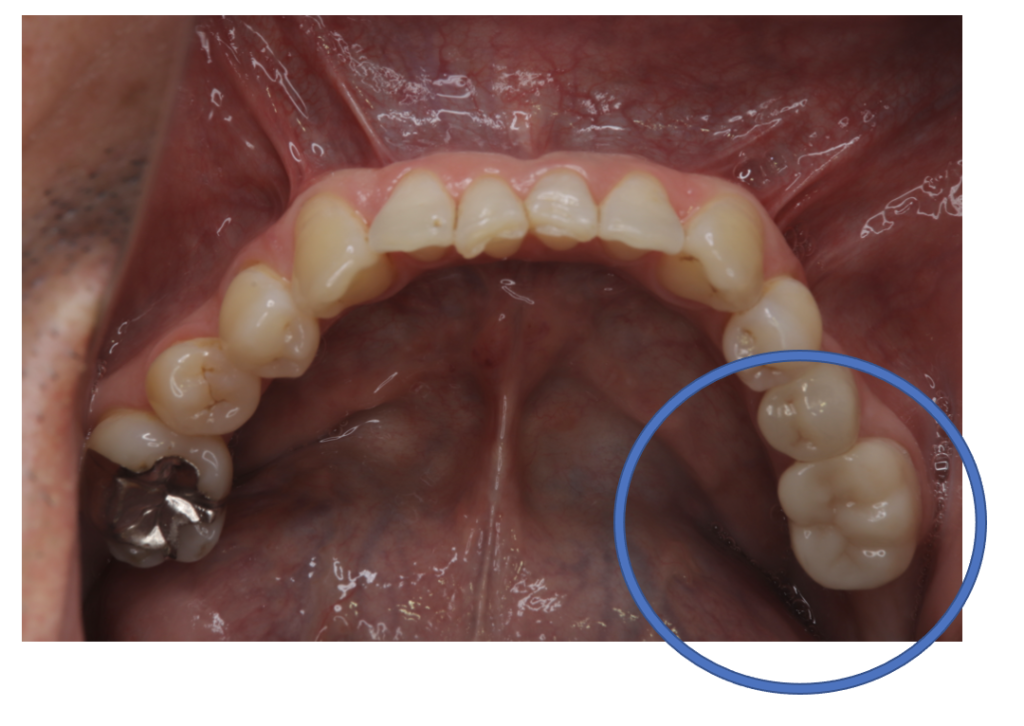

After

| 備考 | 院長より 銀の詰め物、プラスチックの詰め物の内部に虫歯が進行してしまっていたケースです。中を開けて見てみると、外から想像するよりもはるかに虫歯が広がってしまっていました。幸運にも神経を保存できたので、生きた臓器としてまだ使うことが可能です。残存歯質がかなり薄く弱くなってしまったので、ジルコニアで2本を被せて守ってあげています。一番奥の歯は内部で虫歯が進行しすぎてて、折れてしまっていて、残念ながら抜歯をしなくてはならない状況でした。 |